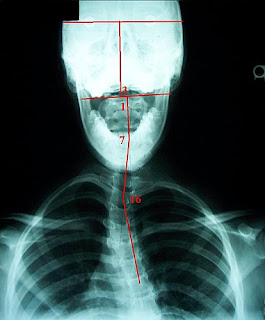

這個部份就是利用光片的分析結果,來進行整脊治療,他們會建議要拍攝各種不同面向的8張X光片,協助分析側彎患者的脊椎偏位。他們的側彎調整手法,不同於一般常見的脊椎側彎調整手法,要先恢復整體的脊椎錯位(global subluxation),即恢復頸椎及腰椎的前彎曲線(lordosis),再來是以一段(segment)、並不是以單一節、一節(unit)的脊椎矯正方式來治療。

簡單來說,是看頭和頸椎的相對位置、第二到第五節頸椎(C2-C5)與第五節頸椎到第二節(C5-T2)的相對位置等,來進行脊椎調整。

左下圖為頭部到胸椎的片段分析(segmental analysis),而右下圖為骨盆和腰椎的片段分析。若能將每段紅線的片段變為相連的一直線(即所有的數字降為0度),脊椎側彎即會消失,便是此種矯正手法的最終目的。